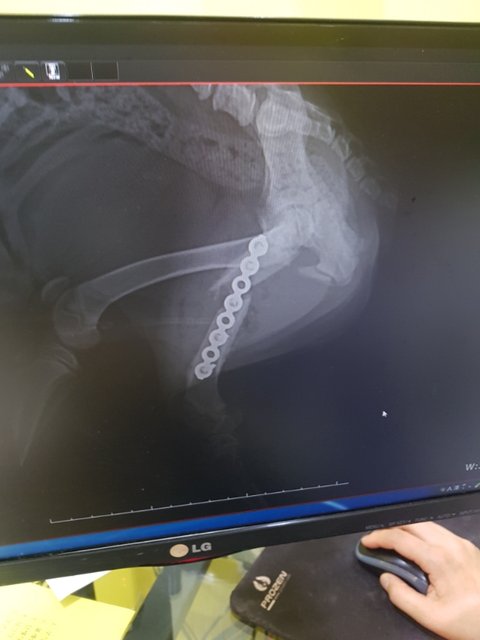

뒷다리골절 수술 무사히 마쳤습니다

골절이 한달정도는 된듯 부러진부분에 지저분하게 뼈조각이며 근육조직들이 엉겨붙어있어 제거하고 수축된 근육을 바로펴 고정하는 수술을 무사히 마쳤습니다